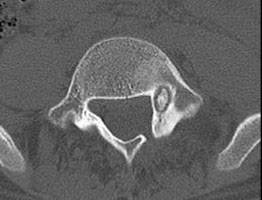

Osteoid osteoma bir kemik tümörü olduğu için tanısı ortopedi uzmanları tarafından konur. Normal kemik röntgen grafisinde görülebilir. Burada görülmezse bilgisayarlı tomografi ya da MR (emar) görüntüleme ile kesin tanı konur.

Tedavi bilgisayarlı tomografi eşliğinde ve tomografi odasında yapılır. Önce kemik tümörünün bilgisayarlı tomografi ile filmleri çekilir, yeri kesinolarak belirlenir. Deriden girim yapılacak nokta uyuşturulur. Biz merkezimide ek olarak sedasyon da yaparız. Bu damardan rahatlatıcı ve ağrı kesici ilaç verilmesidir. Hasta kısa süreliğine bu yöntemle uyutulabilir. Sonra görüntülere bakılarak kemik tümörü içine bir radyofrekans iğnesi ile girilir. Bu iğne 1 mm kalınlığındadır. Radyofrekans enerjisi ile iğne ucunda tümörün içine ısı verilir ve tümör yakılarak tedavi edilir. Ağrı genellikle ilk 3 günde tümüyle kaybolur ancak 2-3 haftaya kadar hafif ağrı devam edebilir.